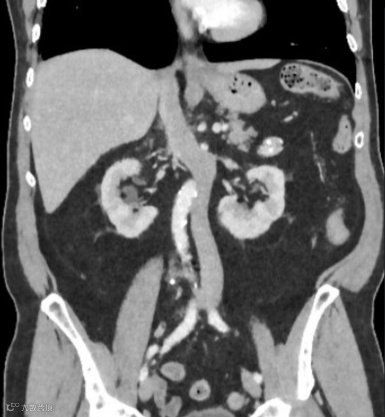

患者,男,60岁,因怀疑主动脉夹层而进行CTA检查,发现马蹄肾,肾峡部可见功能性肾实质,由三条肾动脉供血(箭头)。